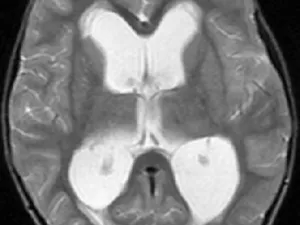

The online fellowship will begin with a comprehensive review of cerebrospinal fluid (CSF) physiology and radiological anatomy. Throughout the fellowship, imaging signs of hydrocephalus will be discussed in detail. Imaging techniques used in the evaluation of hydrocephalus will constitute a major component of the program.

In addition, other CSF disorders—including idiopathic intracranial hypertension, spontaneous intracranial hypotension, and normal pressure hydrocephalus—will be addressed in dedicated sessions, with emphasis on their characteristic radiological findings. Various secondary causes of hydrocephalus, such as leptomeningeal carcinomatosis, tumors, and other obstructive or infiltrative processes, will also be highlighted.

· Become familiar with normal CSF radiological anatomy · Recognize and interpret imaging findings used in the diagnosis of hydrocephalus · Differentiate between the various types of hydrocephalus · Understand the role, advantages, and limitations of different MR imaging modalities in the diagnosis and differential diagnosis of hydrocephalus subtypes · Diagnose other CSF disorders, including idiopathic intracranial hypertension, spontaneous intracranial hypotension, and normal pressure hydrocephalus, based on their radiological features · Identify a wide range of diseases and pathological processes that may cause hydrocephalus · Recognize normal post-treatment imaging appearances in hydrocephalus and identify treatment-related complications

• Structured lectures on CSF physiology, radiological anatomy, and the spectrum of hydrocephalus • In-depth sessions on imaging findings and classification of different types of hydrocephalus • Detailed review of MR imaging techniques and advanced modalities used in the diagnosis and differential diagnosis of hydrocephalus • Dedicated modules on other CSF disorders, including idiopathic intracranial hypertension, spontaneous intracranial hypotension, and normal pressure hydrocephalus • Case-based discussions and real-life imaging examples to reinforce key concepts • Focused lectures on secondary causes of hydrocephalus, such as tumors, leptomeningeal carcinomatosis, and other obstructive or infiltrative pathologies • Review of normal post-treatment imaging appearances and recognition of treatment-related complications